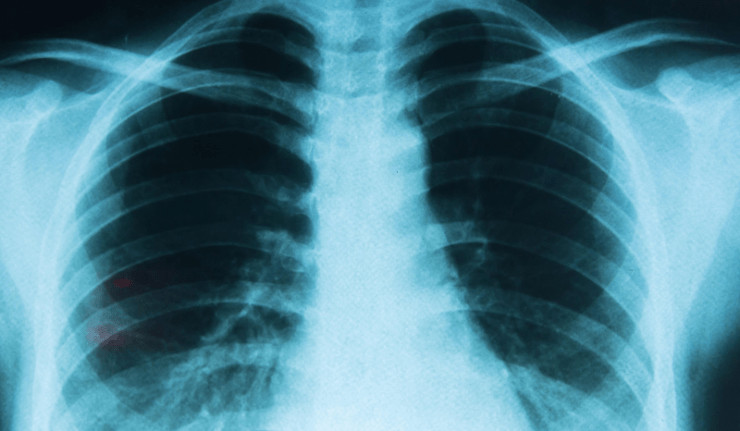

Une étude menée en Corée du Sud auprès de 8,4 millions de personnes (2021-2023) montre une augmentation significative de plusieurs cancers seulement un an après la vaccination : Thyroïde : +35% Gastrique : +34% Colorectal : +28% Poumon : +53% Poitrine : +20% Prostate : +69%

Les HR de la thyroïde (HR, 1,351 ; IC à 95%, 1,206-1,514), gastrique (HR, 1,335 ; IC à 95%, 1,130-1,576), colorectal (HR, 1,283 ; IC à 95%, 1,122-1,468), pulmonaire (HR, 1,533 ; IC à 95%, 1,254-1,874), mammaire (HR, 1,197 ; IC à 95%, 1,069-1,340) et prostatique (HR, 1,687 ; IC à 95%, 1,348-2,111)